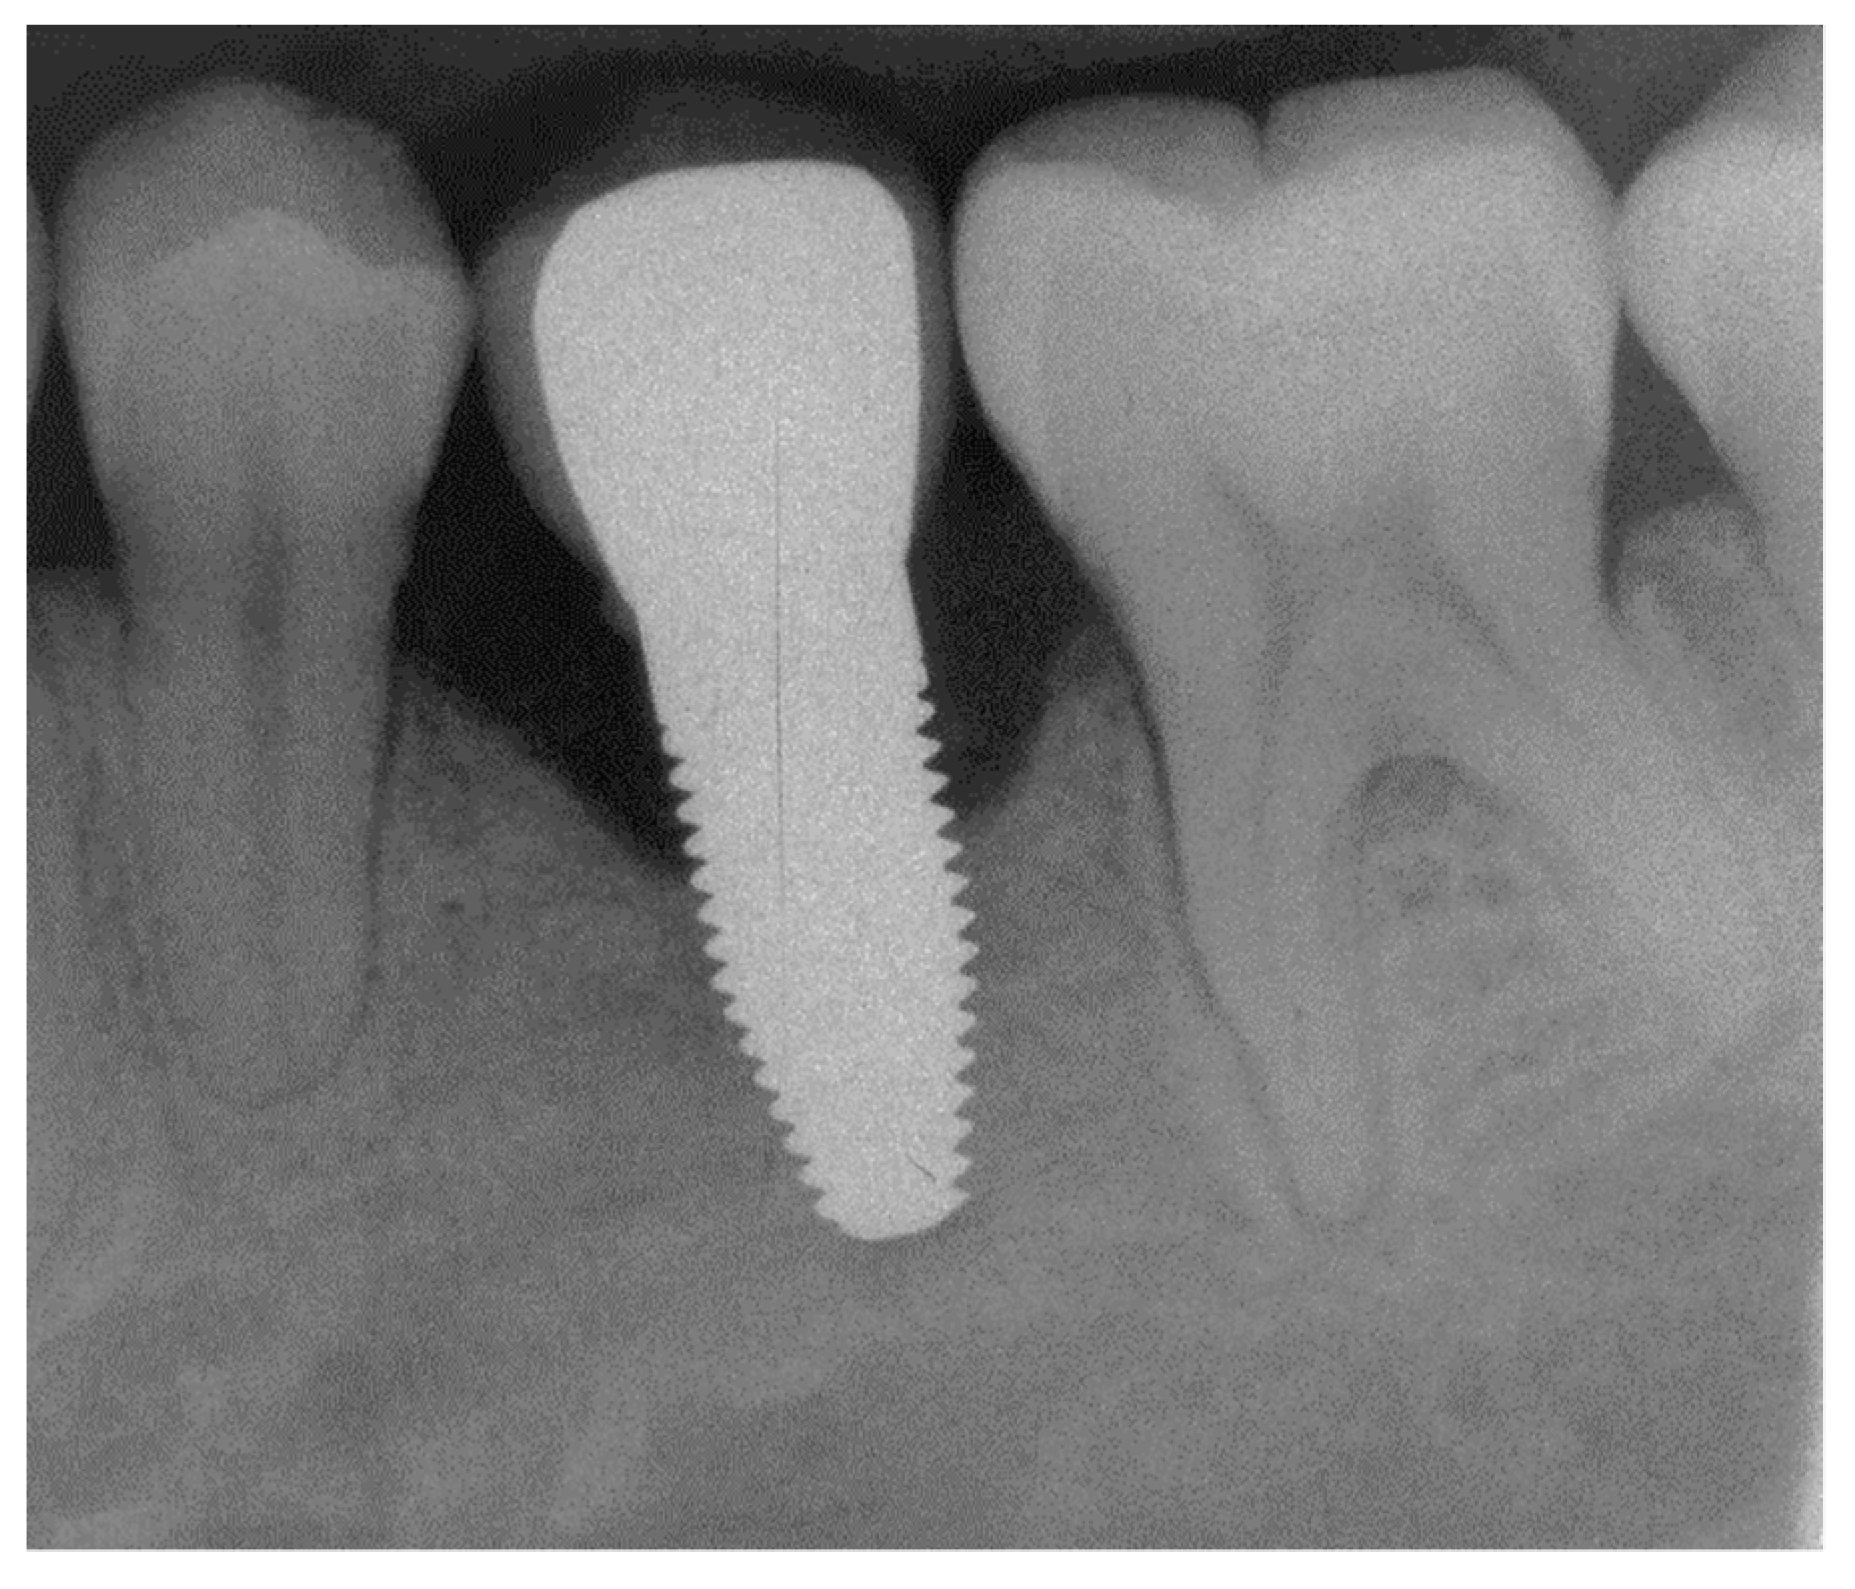

Appendix B. Exemplary Photographs and Radiographs from a Patient at Different Examination Time Points and a More Negative Outcome